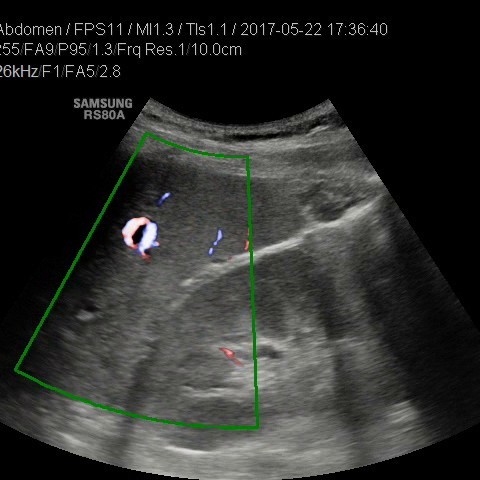

• USG jamy brzusznej

z oceną wątroby, trzustki, nerek, śledziony, pęcherza, gruczołu krokowego, dużych naczyń jamy brzusznej oraz przestrzeni okołoaortalnej.

• USG doppler naczyń

kończyn górnych i dolnych - żylnych lub tętniczych

• USG jamy brzusznej z oceną wątroby, trzustki, nerek, śledziony, pęcherza, gruczołu krokowego, dużych naczyń jamy brzusznej oraz przestrzeni okołoaortalnej

• USG doppler aorty i naczyń biodrowych

• USG doppler układu wrotnego

Rozszerzamy ofertę naszych pracowni: